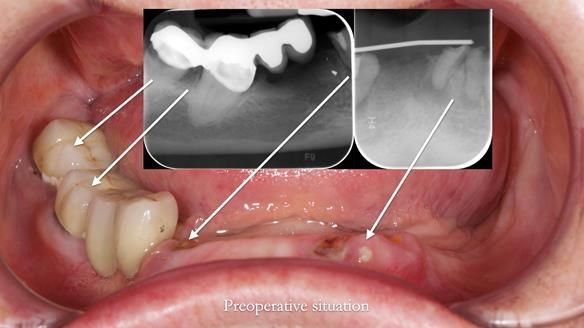

- Extraction of lower 32, 33, 47 and 43

However, once Rowan and I reviewed the remaining metal crown on tooth 46, we realised it would make an ideal abutment for a gasket denture. By reshaping the lingual surface of the crown, we created an excellent gasket seal.

This approach worked far better than the proposed ring-clasp design - improving retention, comfort, and aesthetics while keeping the design clean and simple.

- The gasket seal around 46 was made using retention.sil 200, producing a precise, cushioned fit.